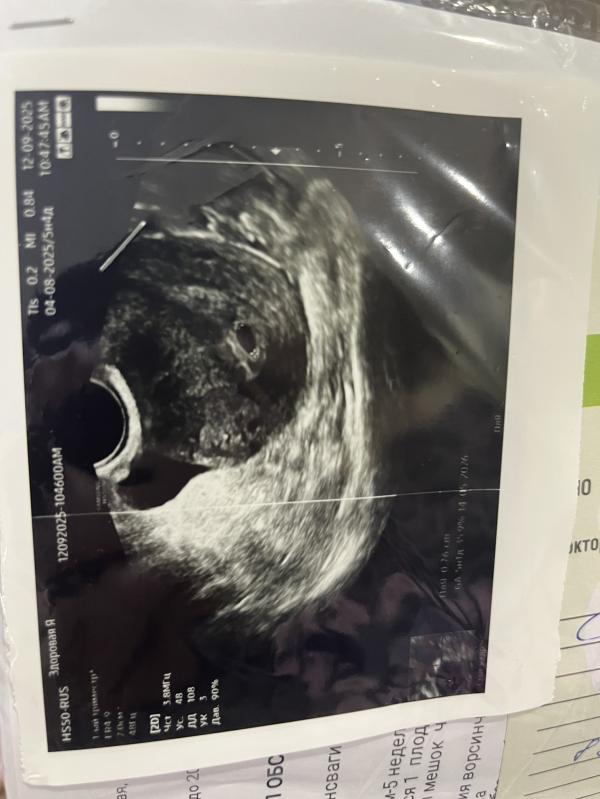

Нашли мою бусинку 😭

Эндометрий как всегда очень тонкий, сразу посадили на дюфастон, но ничего , двоих выносила с тонким эндометрием, и с этим надеюсь смогу ☺️

Да, у меня поздняя овуляция, эмбрион всегда появляется только в 7 недель)